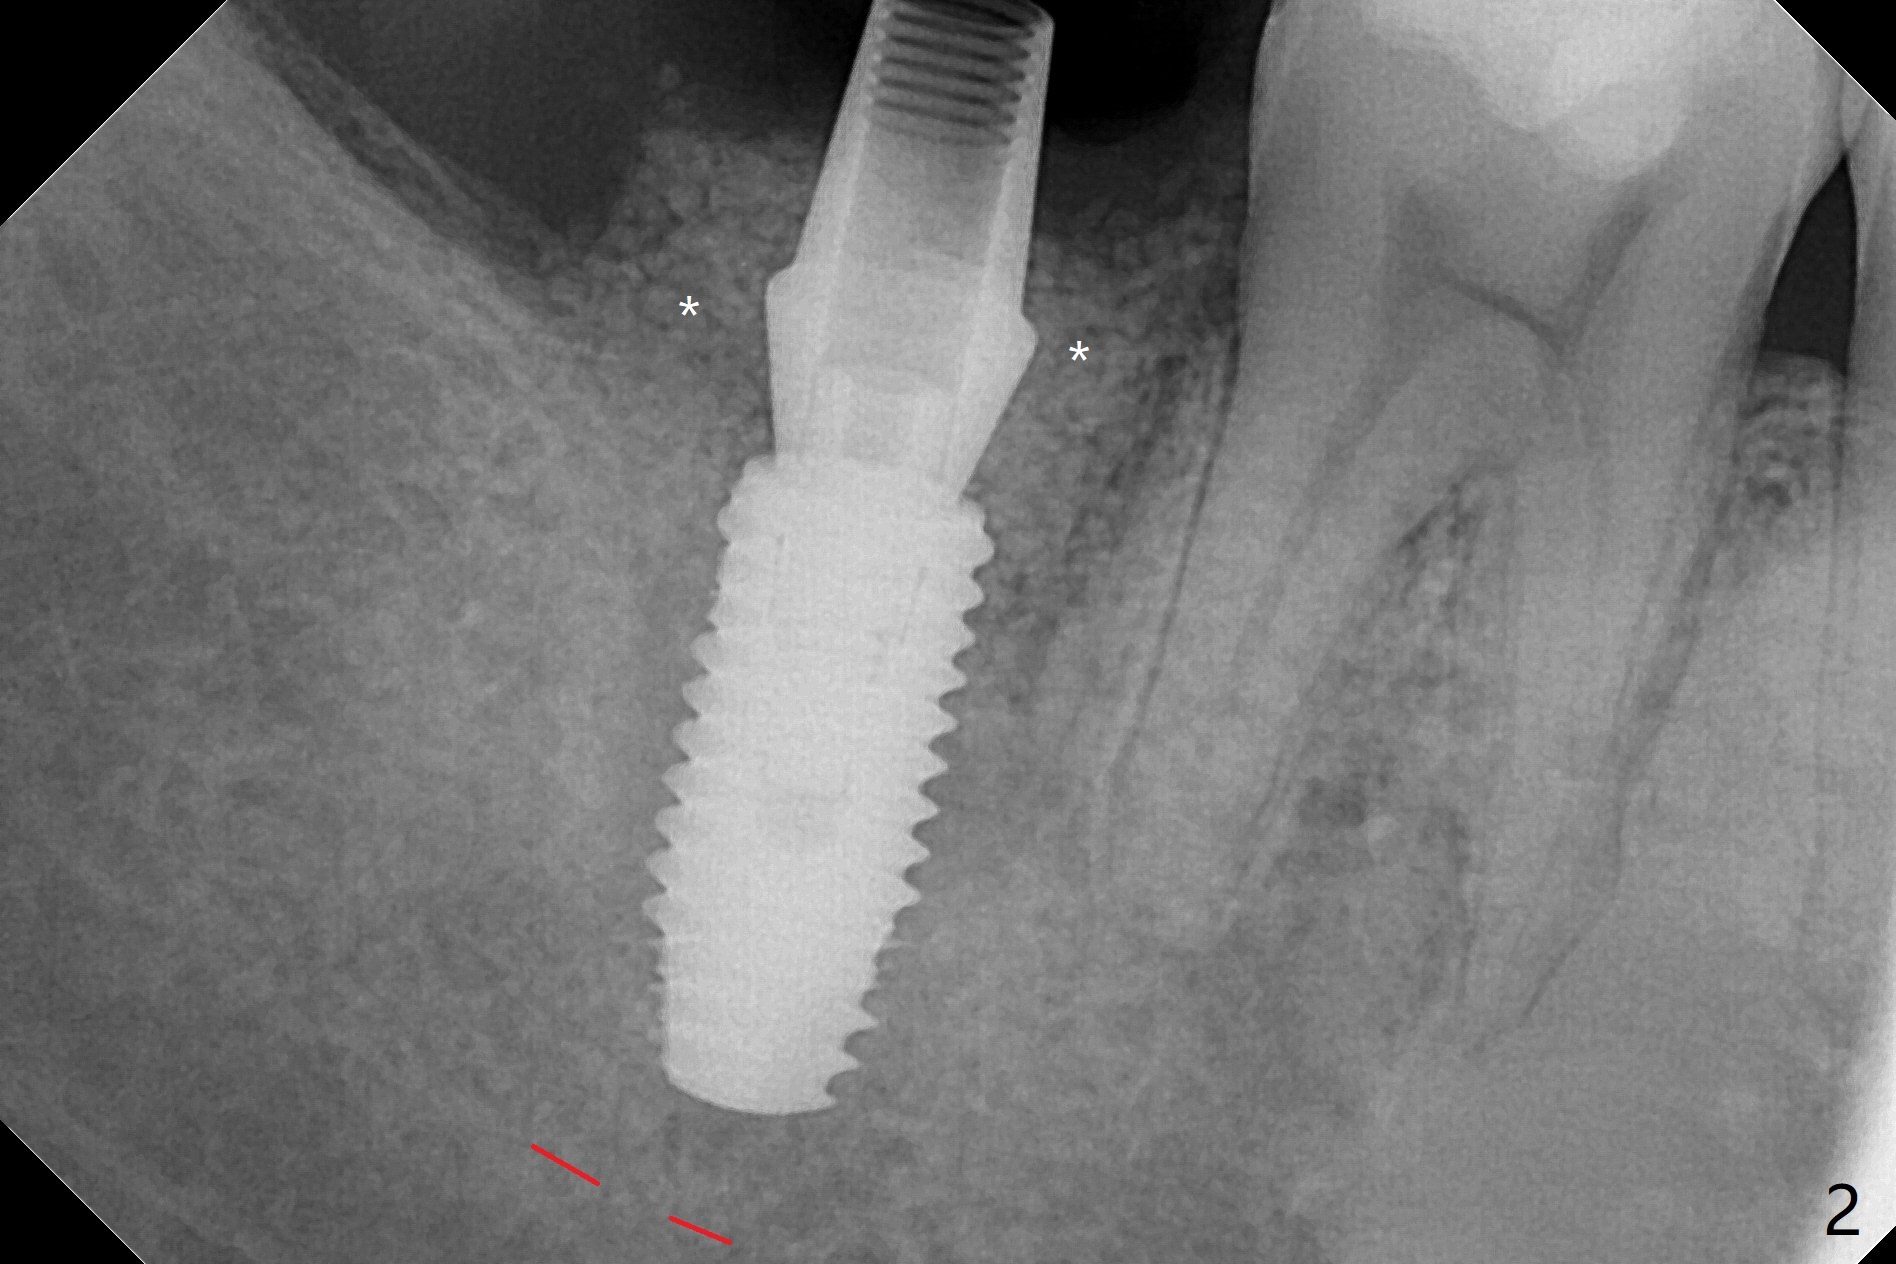

右下七5x11.5毫米植体导板植入根尖骨质大约2-3毫米(图一),扭力~50 Ncm,即使发生骨坏死,不会产生植体周围炎,最坏植体松动脱落。放置基台后,植入大量粘性骨粉(图二:*),覆盖PRF(图三);如果使用临时牙冠关闭牙槽窝,牙冠与龈缘(箭头)接触不紧,使用水牙线冲洗,骨粉流失严重。所以采纳树脂敷料(图四:A),后者边缘至少覆盖牙槽窝口1-2毫米,一周复查,及时关闭术后牙龈退缩所造成的漏洞。其实病人术后第二天回来,敷料脱落,理由:远中无牙,基台短(图五)。Return to Prevent Molar Periimplantitis (Protocols, Table) Protect Graft Torque 第一磨牙即种 Xin Wei, DDS, PhD, MS 1st edition 04/27/2021, last revision 04/29/2021